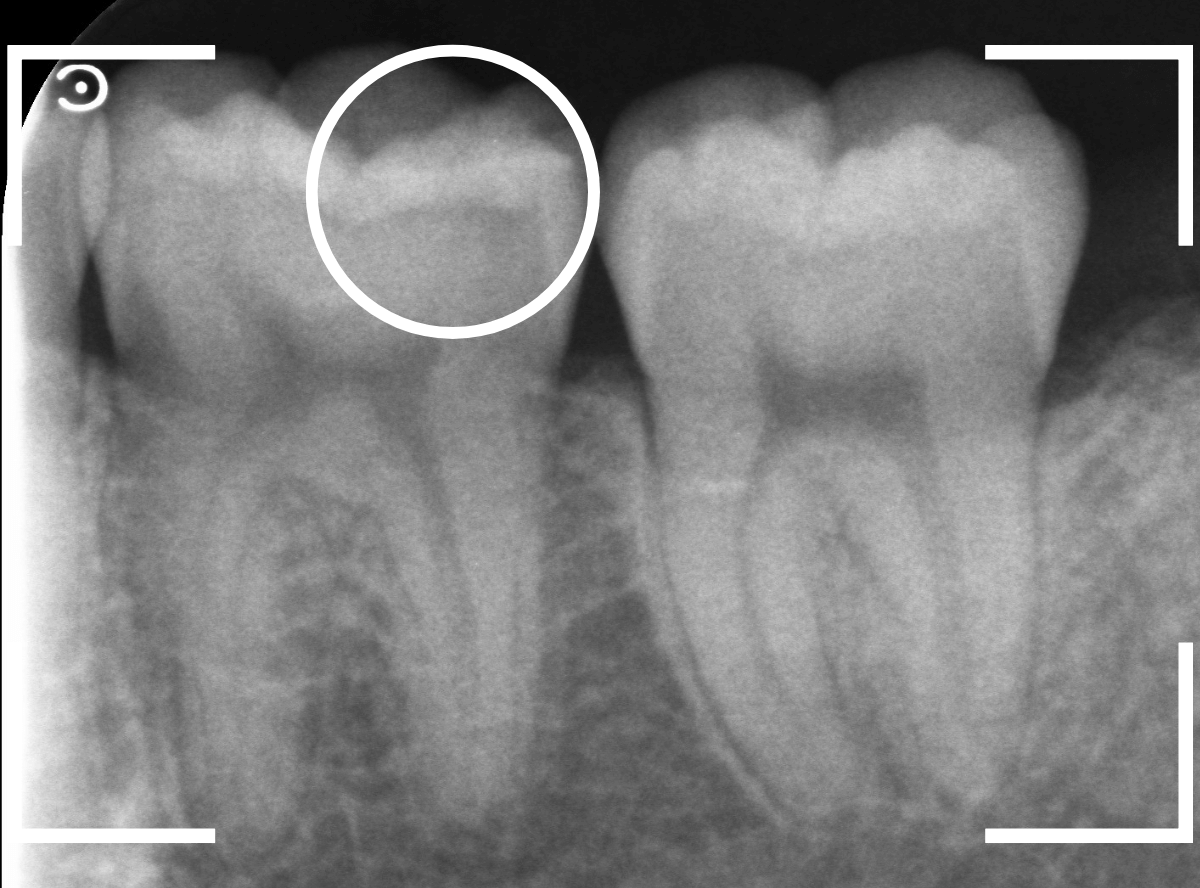

Case.8 大きな虫歯なのに、レントゲンではっきり写らない

こちらも定期検診希望で来院された患者さんです。

お口の中を拝見すると、明らかに虫歯がありました。

3本虫歯になっており、特に中央の小臼歯はかなり大きな虫歯になっているのが予想されます。

治療前にレントゲン写真で虫歯の大きさを確認するつもりが・・・あまりはっきり写ってきません。

患者さんに状況を説明して、歯を少しずつ削りながら虫歯を確認する事になりました。

まず、一番大きな虫歯と思われる部分を小さく削って確認します。

予想通り、虫歯が見えてきました。

隣りの奥歯と一緒に虫歯の治療を進めます。

色が染まっているところがまだ虫歯が残っている部分です。

2本とも、虫歯を全て取り切りました。

特に手前の歯はかなり広めの虫歯になっていました。

最終的に、手前の虫歯の除去も終わったところです。

手前の歯の虫歯は中央の歯まで達していました。

このように明らかに大きな虫歯があると診断されるような状況でも、レントゲン写真でうまく診断できない場合もあります。